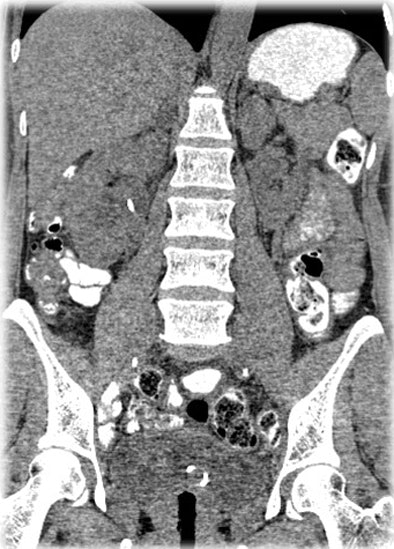

| Filtered back projection (above) and MBIR (below) reconstructed from the same raw dataset and the following acquisition parameters: 120 kVp, 75 mAs, and 64 x 0.625 mm. Note the small low-attenuation mass in the right adrenal gland on the MBIR image (arrow). All images courtesy of Dr. Rendon Nelson. |